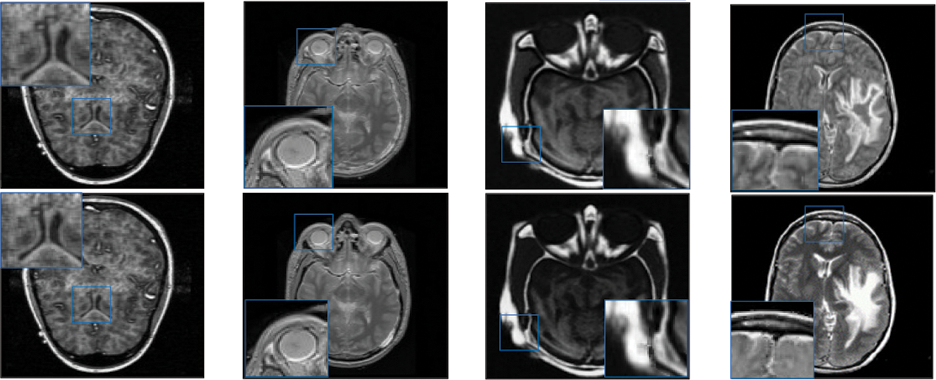

In this study, eight pairs of medical images are employed during the experiments to validate the practicability and feasibility of our algorithm. A total of eight pairs of CT-MRI images are demonstrated in Fig. 2. All these test datasets contain a spatial resolution of 256 × 256 pixels. Further, seven existing comparative methods are utilized for comparison to assess the robustness of our approach, including the adolescent identity search algorithm in the NSST domain (AISA-NSST) [28], the medical image fusion method by deep learning (MIFDL) [40], multi-objective differential evolution based deep neural networks (MDE-DNN [41], geometric algebra discrete cosine metrics (GADCT) [43], medical assistive technology management based on hybrid domain filtering (MATM-HDF) [8], FDGNet [57] and sparse representation and Siamese convolutional neural network (SRSCNN [58]. All the experiments are performed on a PC with an Intel (R) Core (TM) i3-7020 CPU @ 2.3 GHz and 8 GB of RAM using MATLAB 2022a. Following [49], the parameter values are fixed at

Figure 2: Source paired images (A–H): CT-MRI image pairs. Top